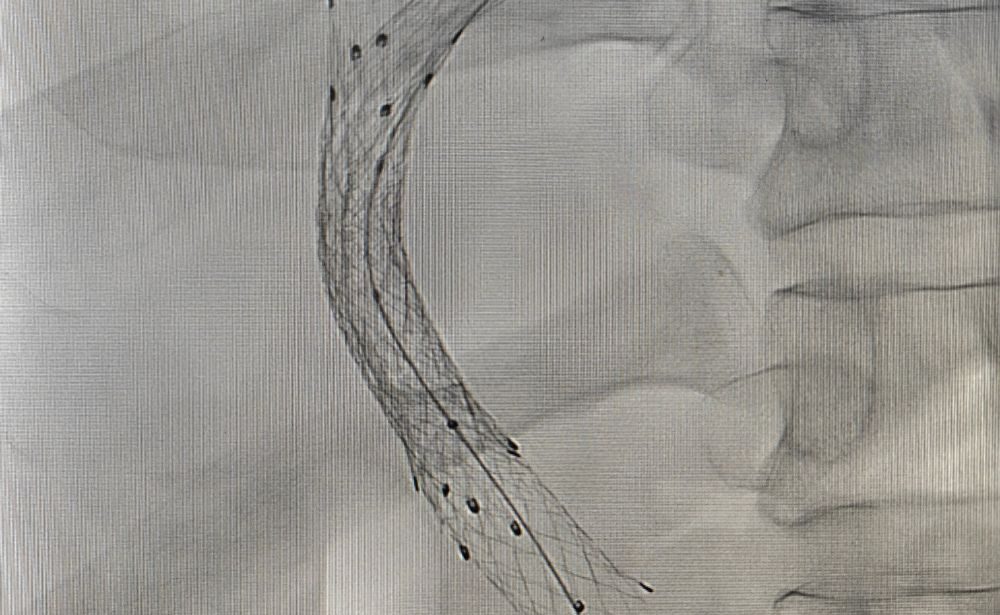

1. TIPS Procedure & TIPS Reduction

The Problem: Severe liver cirrhosis can cause critically high blood pressure in the portal vein (portal hypertension), leading to life-threatening complications like variceal bleeding or stubborn fluid buildup in the abdomen (ascites) that doesn’t respond to medication.

Our Solution: The TIPS (Transjugular Intrahepatic Portosystemic Shunt) procedure creates a new channel within the liver to divert blood flow and reduce this dangerous pressure. If the shunt becomes too wide and causes complications, a TIPS Reduction procedure can be performed to adjust its size and restore balance.

Patient Benefit: A life-saving intervention for uncontrolled bleeding and a highly effective treatment for debilitating ascites.